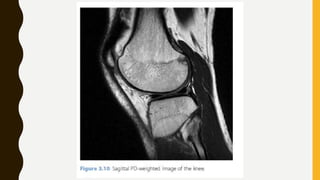

PD-Weighted Images

• We have already introduced two fundamental properties of tissues in the body: T1 and

T2 relaxation, which are used to create contrast in MR imaging.

• The third important property is the proton density, PD.

• Proton density is essentially the water content of the tissues, and so it does not vary

much, ranging from 75% to 85% in most organs.

• Although this limited range means that PD scans are rather ‘grey’, i.e. lack contrast,

compared with T1w or T2w scans, they have some useful clinical applications; for

example, in the knee you can distinguish articular cartilage from the cortical bone and

menisci .

• PDw images can be produced either with SE or GE sequences; however, for

musculoskeletal imaging it is usual to stick to SE.